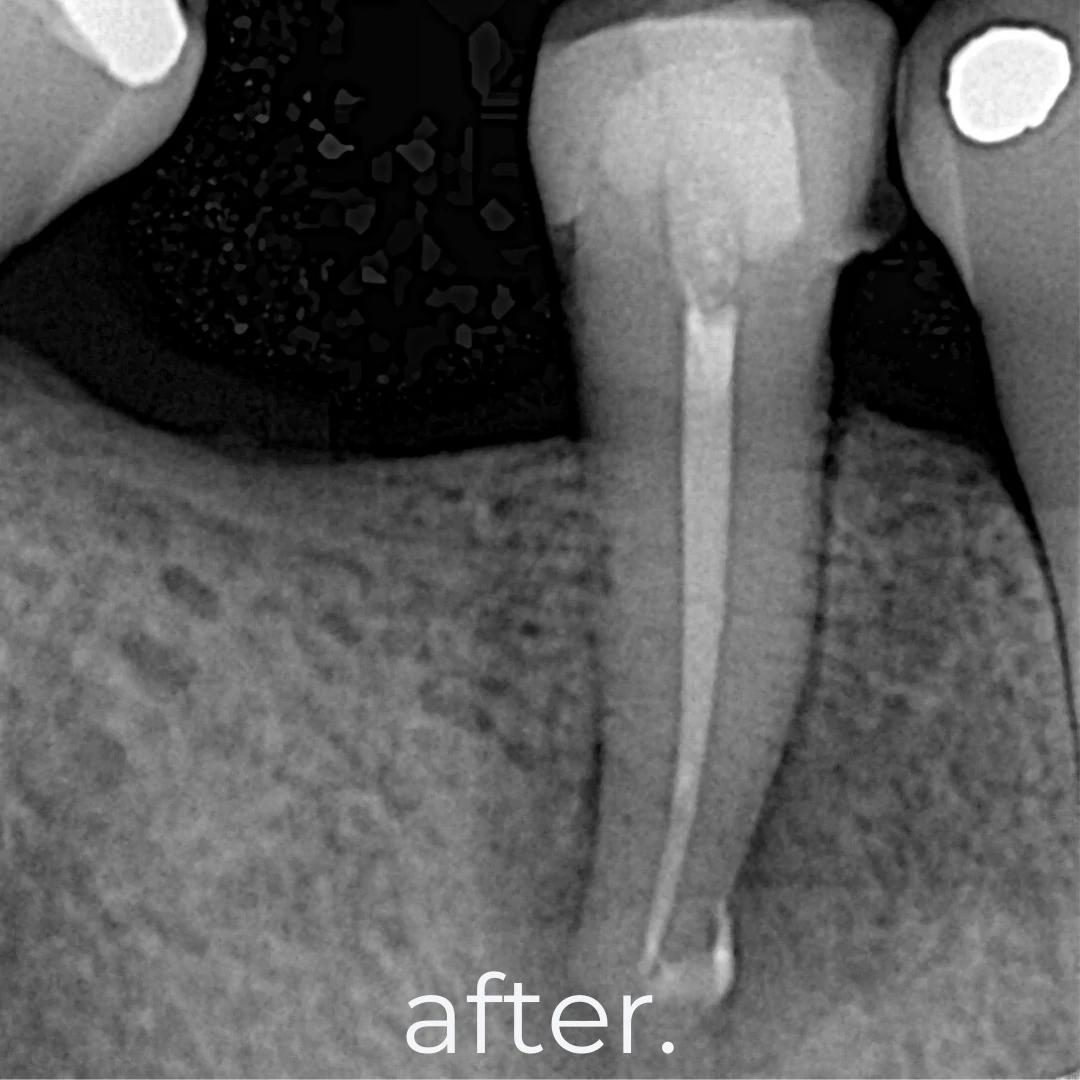

A root canal treatment is a minimally invasive procedure designed to remove infected or inflamed dental pulp, disinfect the root canal, and seal it with a biocompatible filling. This treatment eliminates pain while preserving your natural tooth structure, preventing the need for extraction and maintaining oral health and function.

🦷 Phase 2: Root Canal Filling & Sealing – Biocompatible material placed for strength

🦷 Phase 3: Final Restoration – Dental crown or filling placement for durability